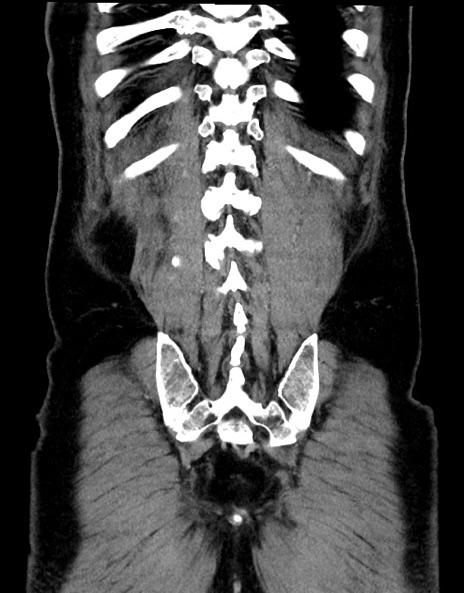

症例15(冠状断像)

【症例】70歳代男性

【主訴】腹痛

【現病歴】今朝から腹痛あり。全体的に痛い。特に左上の方。排ガスが今日はない。冷や汗が出る。

【既往歴】直腸癌術後

【身体所見】左側腹部〜上腹部に圧痛あり。腹膜刺激症状明らかなではない。軽度反跳痛。左下腹部に術後瘢痕あり。

【データ】WBC 7700、CRP 0.02